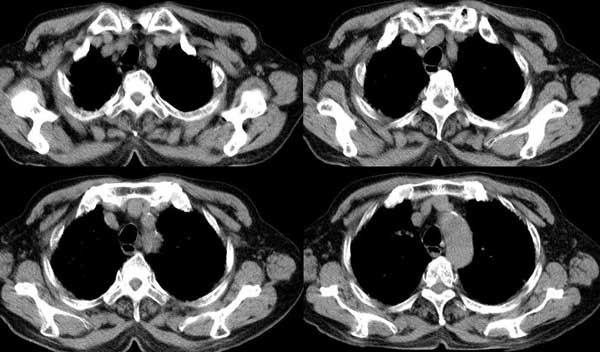

以下是引用dalianren在2006-7-20 21:23:00的发言:[br]我考虑是肺泡蛋白沉积症:典型表现为两肺内散在片状\"磨玻璃\"样混浊区呈地图样分布.

以下是引用lj0804在2006-7-21 12:57:00的发言:[br]支持[br]我考虑是肺泡蛋白沉积症:典型表现为两肺内散在片状\"磨玻璃\"样混浊去呈地图样分布.